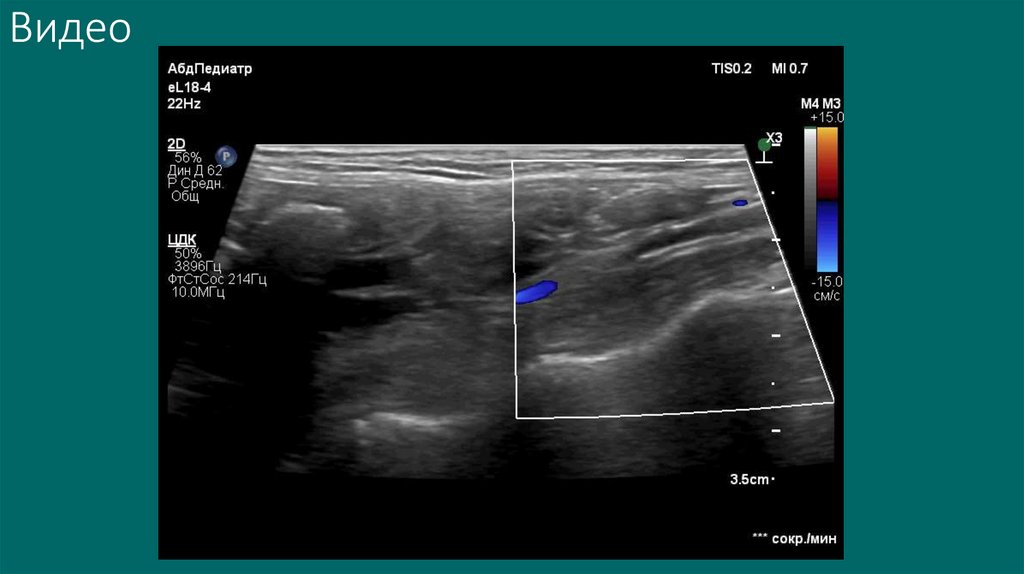

Видео